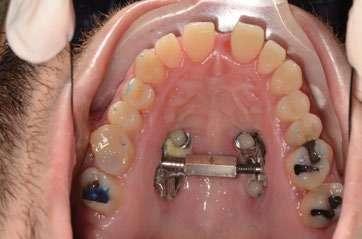

Fase 1: disyunción con MARPE

Tras colocar la anestesia palatina infiltrativa, el disyuntor osteo-soportado con tornillo hexagonal, se fijó de forma segura mediante los mini-tornillos utilizando un contra-ángulo de baja velocidad. Ese mismo día, se inició la expansión con pauta de 1 vuelta al día (0,16 mm por vuelta). Tras 43 días, se apreció la apertura de diastema inter-incisal y se continuó dando vueltas durante 18 días más hasta conseguir la corrección de la mordida cruzada posterior (Ilustración 5).

Ilustración 4. Registros radiográficos iniciales de estudio.

El paciente fue instruido en la higiene del dispositivo para evitar inflamación gingival y se realizaron controles rutinarios cada dos semanas. Al finalizar el procedimiento de expansión, el paciente fue monitoreado durante 75 días.

Evidencia clínica y radiográfica de la expansión:

 Separación visible de incisivos centrales, indicativa de apertura de la sutura palatina.

 Expansión confirmada mediante superposición de los modelos maxilares digitales previos y posteriores al tratamiento mediante MARPE (Ilustración 6). Se obtuvo un aumento transversal del 5,14 mm a nivel de los primeros molares.

Ilustración 5. Fotografías intraorales tras la disyunción con MARPE.